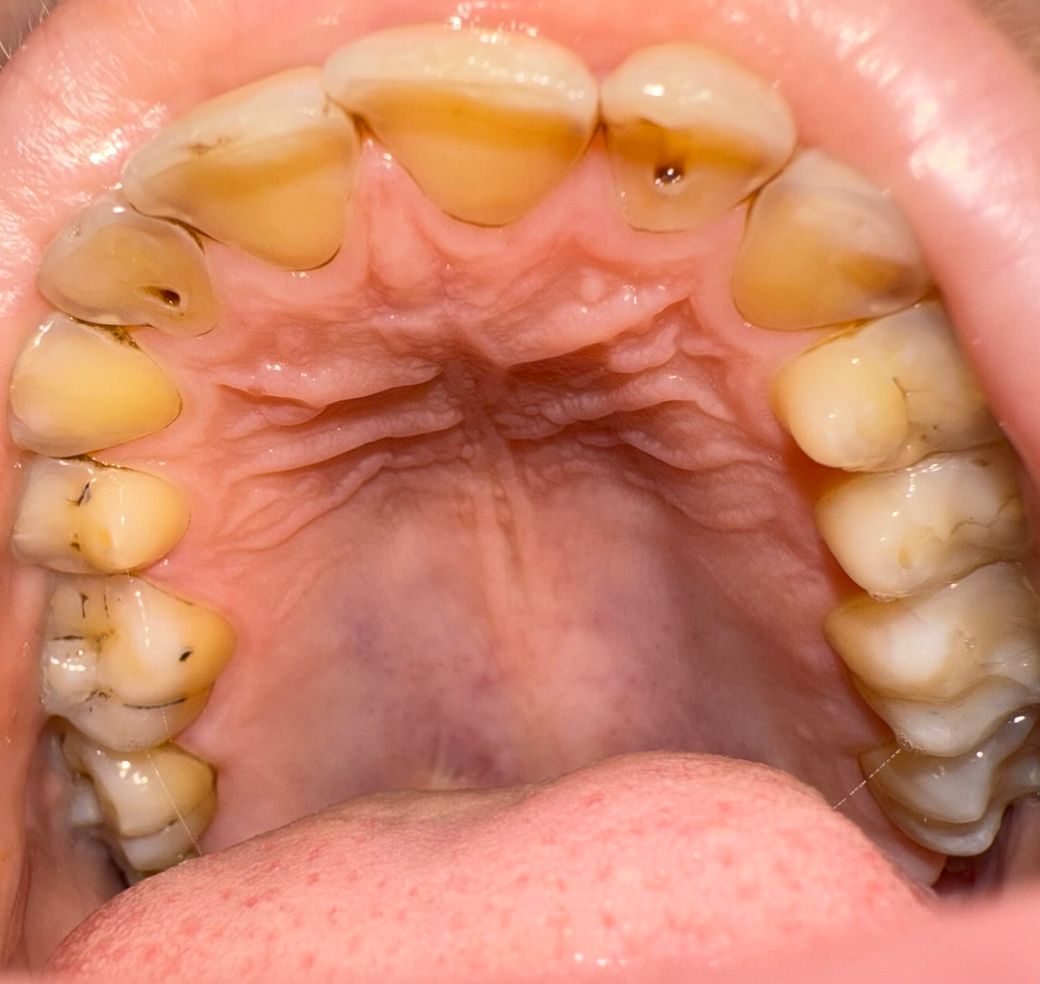

치과 어느정도의 치료가 필요한지 궁금합니다

아랫니만 치료를 하고 윗니는 방치했다가 최근에 사진을 찍어보니 이렇습니다.

이정도면 어느정도 치료를 해야하는지 궁금합니다

치아의 전반적인 충치가 보입니다. 우선 충치 치료를 해야 될 것으로 보입니다. 치아의 설면이 마모가 많이 되어 있는 듯 보입니다. 경우에 따라서는 크라운과 같은 보철치료를 해야 할 수 있습니다.

초기충치와 다소 진행된 충치가 여러개 있고 충치치료, 신경치료 가능성이 있어보입니다.